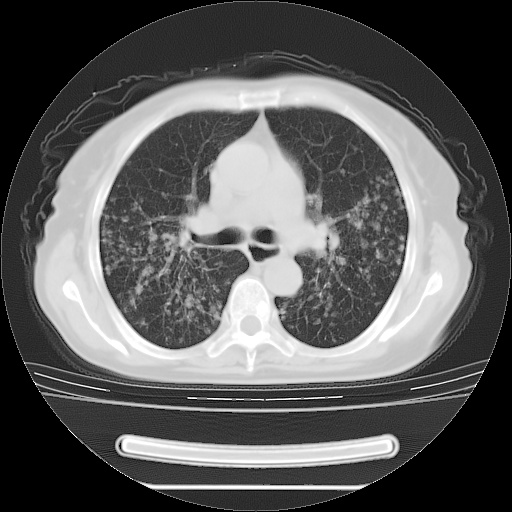

患者女性,72岁,慢性咳嗽3月余,曾抗炎治疗无效果,最近抗结核治疗约半月余,症状缓解。

ct示两肺粟粒状病灶,以两肺上叶尖后段及下叶背段分布为主;首先考虑结核。请战友们分析。

考虑 1 弥漫性泛细支气管炎, 2 结核不除外/.  有小叶中心结节 和 树芽征!!

两肺内病灶呈小结节状和树芽状,纵膈的肿大的淋巴结密度不均匀,并见有钙化,考虑为两肺结核可能更大些。

两肺内病灶呈小结节状和树芽状,纵膈的肿大的淋巴结密度不均匀,并见有钙化,多形态病灶,考虑为两肺结核,肝内考虑小囊肿。

病灶以结节为主,大部分边界清楚,分布不均,病灶形态较单一,偶见空泡征,纵膈淋巴结肿大钙化,无结核中毒症状考虑 感染性病变【真菌类可能性大】,细支气管肺泡癌。其他待排

片子很好,质量很高,两侧肺门淋巴结肿大并有钙化,两肺弥漫病灶,首先考虑tb并播散,但年龄大了呀(72岁)小细胞肺癌不能除外,如果是肺癌也没什么大的治疗了,建议正规抗结核治疗后复查

纵隔见肿大淋巴结并钙化,首先考虑结核,但感觉小结节像“挂果”征,分布位于支气管边缘,所以不排外肺泡癌,建议抗唠后复查吧?不然是癌的话,也不好治吧?化疗?